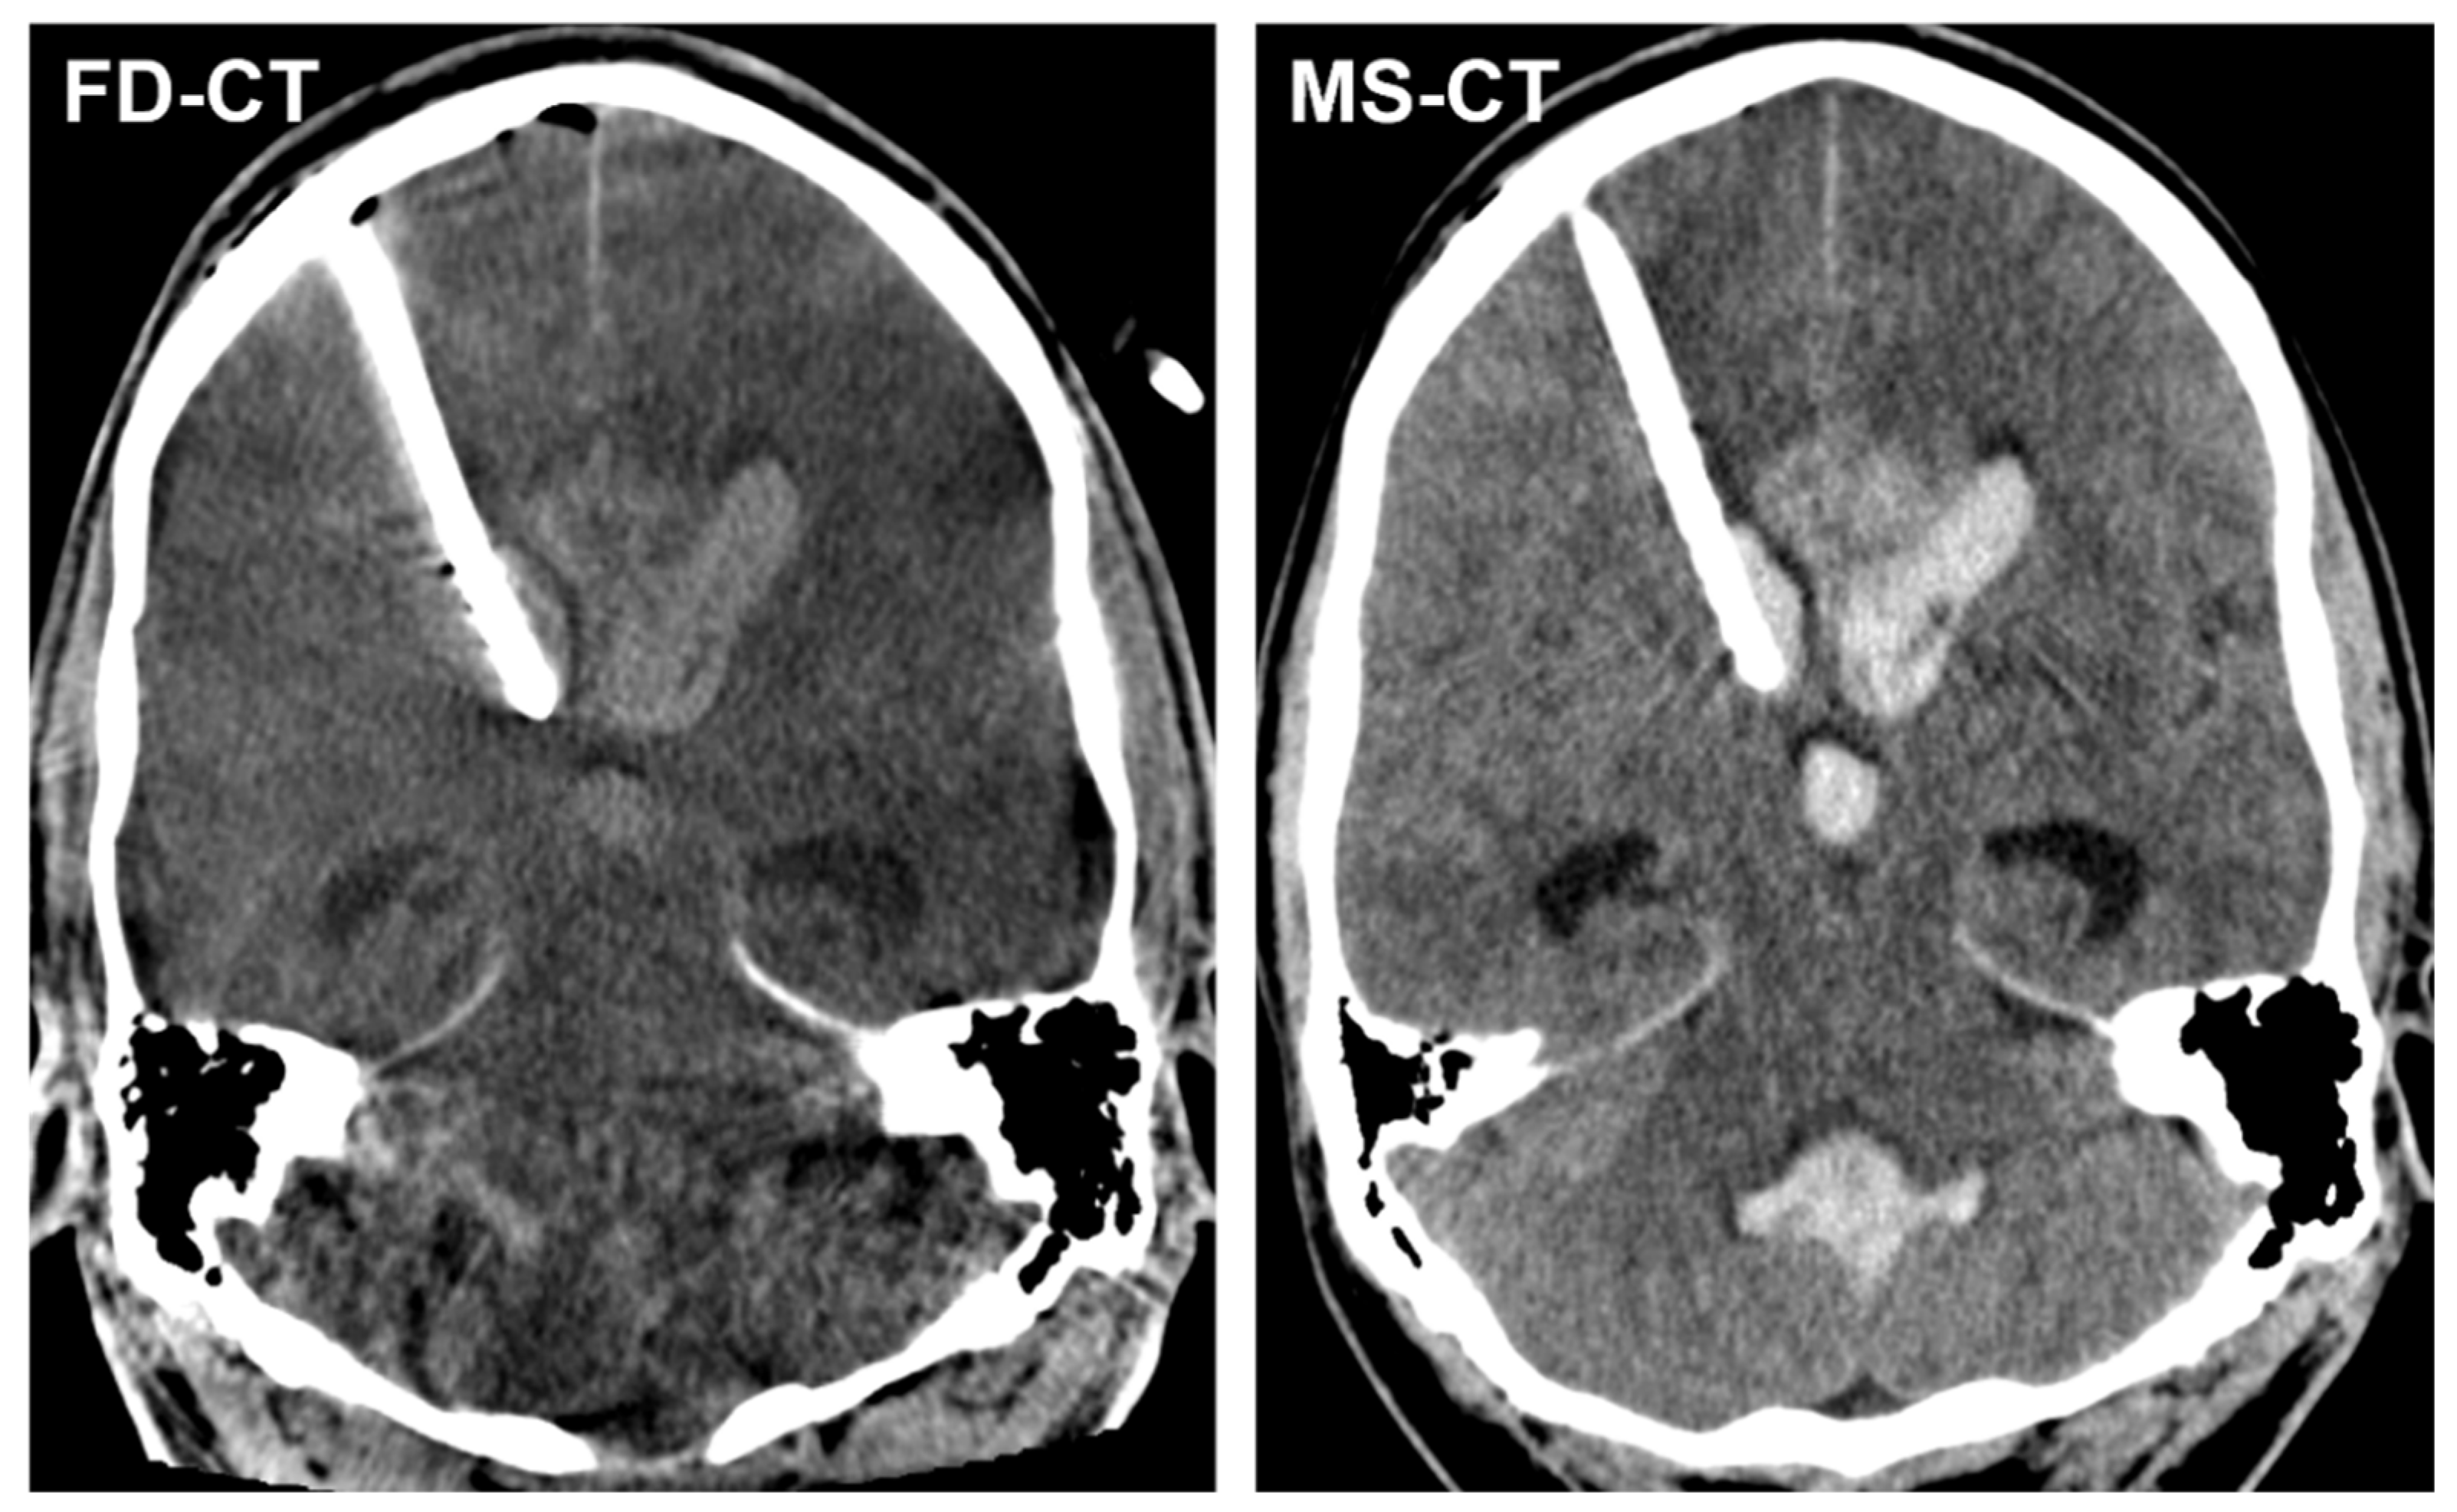

3.3.2. External Ventricular Drain Position